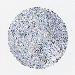

PANCREATIC CANCER - Protein expressioni

A mouse-over function shows sample information and annotation data. Click on an image to view it in a full screen mode. Samples can be filtered based on level of antibody staining by selecting one or several of the following categories: high, medium, low and not detected. The assay and annotation is described here.

Note that samples used for immunohistochemistry by the Human Protein Atlas do not correspond to samples in the TCGA dataset.

Antibody stainingi

Antibody staining in the annotated cell types in the current human tissue is reported as not detected, low, medium, or high, based on conventional immunohistochemistry profiling in selected tissues. This score is based on the combination of the staining intensity and fraction of stained cells.

Each image is clickable and will lead to virtual microscopy that enables deeper exploration of all samples and also displays staining intensity scores, fraction scores and subcellular localization as well as patient and tissue information for each sample.

Staining

High

Medium

Low

Not detected

Intensity

Strong

Moderate

Weak

Negative

Quantity

>75%

75%-25%

<25%

None

Location

Nuclear

Cytoplasmic/membranous

Cytoplasmic/membranous,nuclear

Adenocarcinoma, NOS